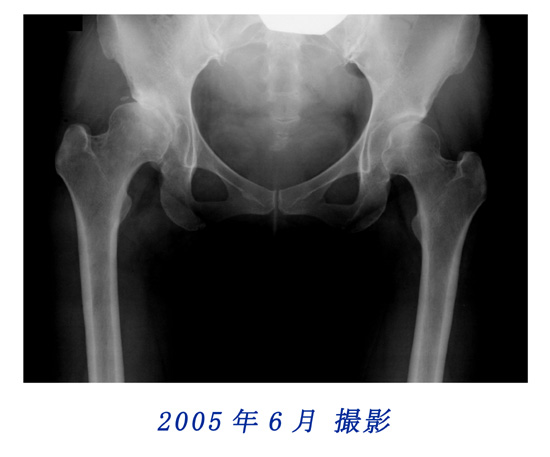

2000年6月と2003年4月のレントゲン写真を比較しても、変化は認めにくいのですが、2003年4月と2005年6月に撮影されたレントゲン写真の骨盤形状に顕著な変化を観察することができます。

比較用レントゲン写真

2003年4月と2005年6月に撮影されたレントゲン写真を重ねてみました。写真にカーソルを重ねると2003年と2005年の写真が入れ替わります。骨盤形状の変化を観察してください。